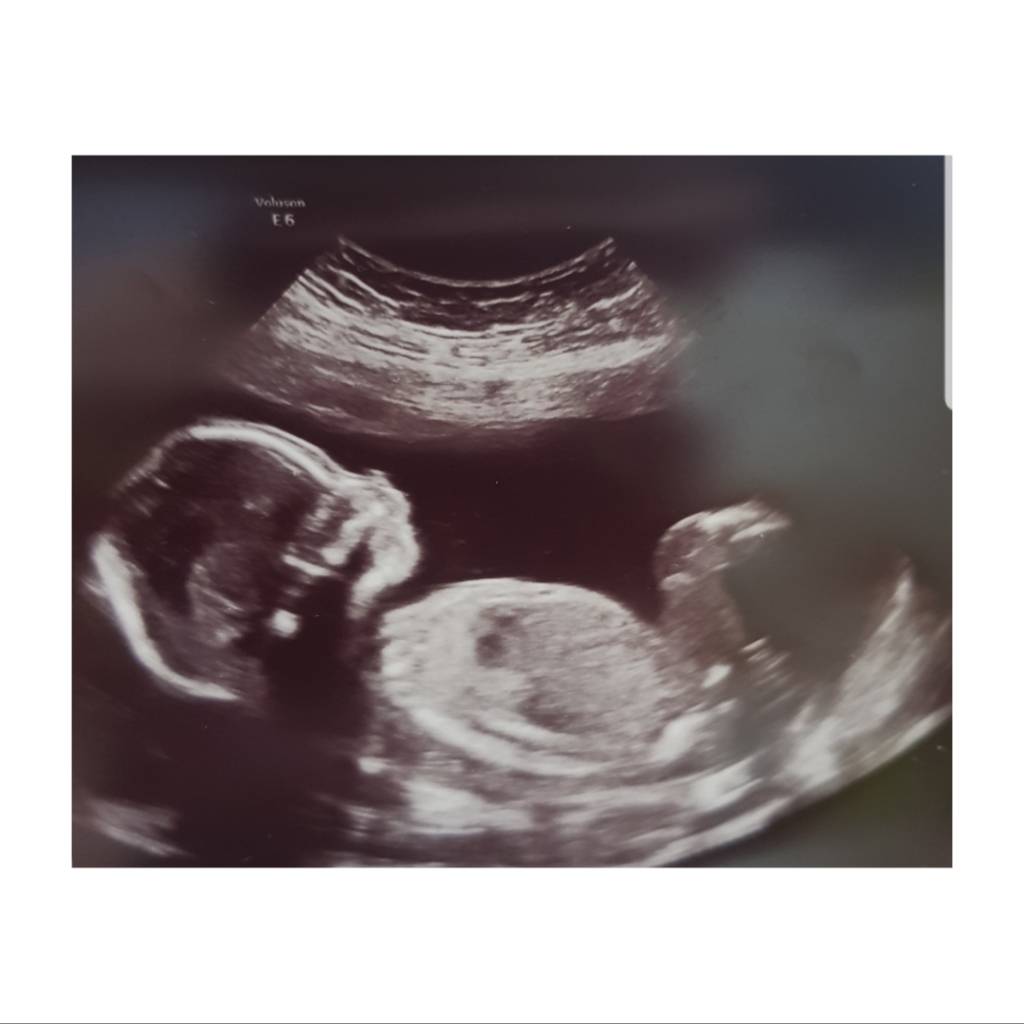

Gratulerer så mye med en liten gutt i magen [emoji170]Alt var kjempefint på oul igår, og vi venter en liten gutt [emoji170]

Ble satt noen dager tilbake, så nå er termin 26 desember [emoji16]Vis vedlegget 268573